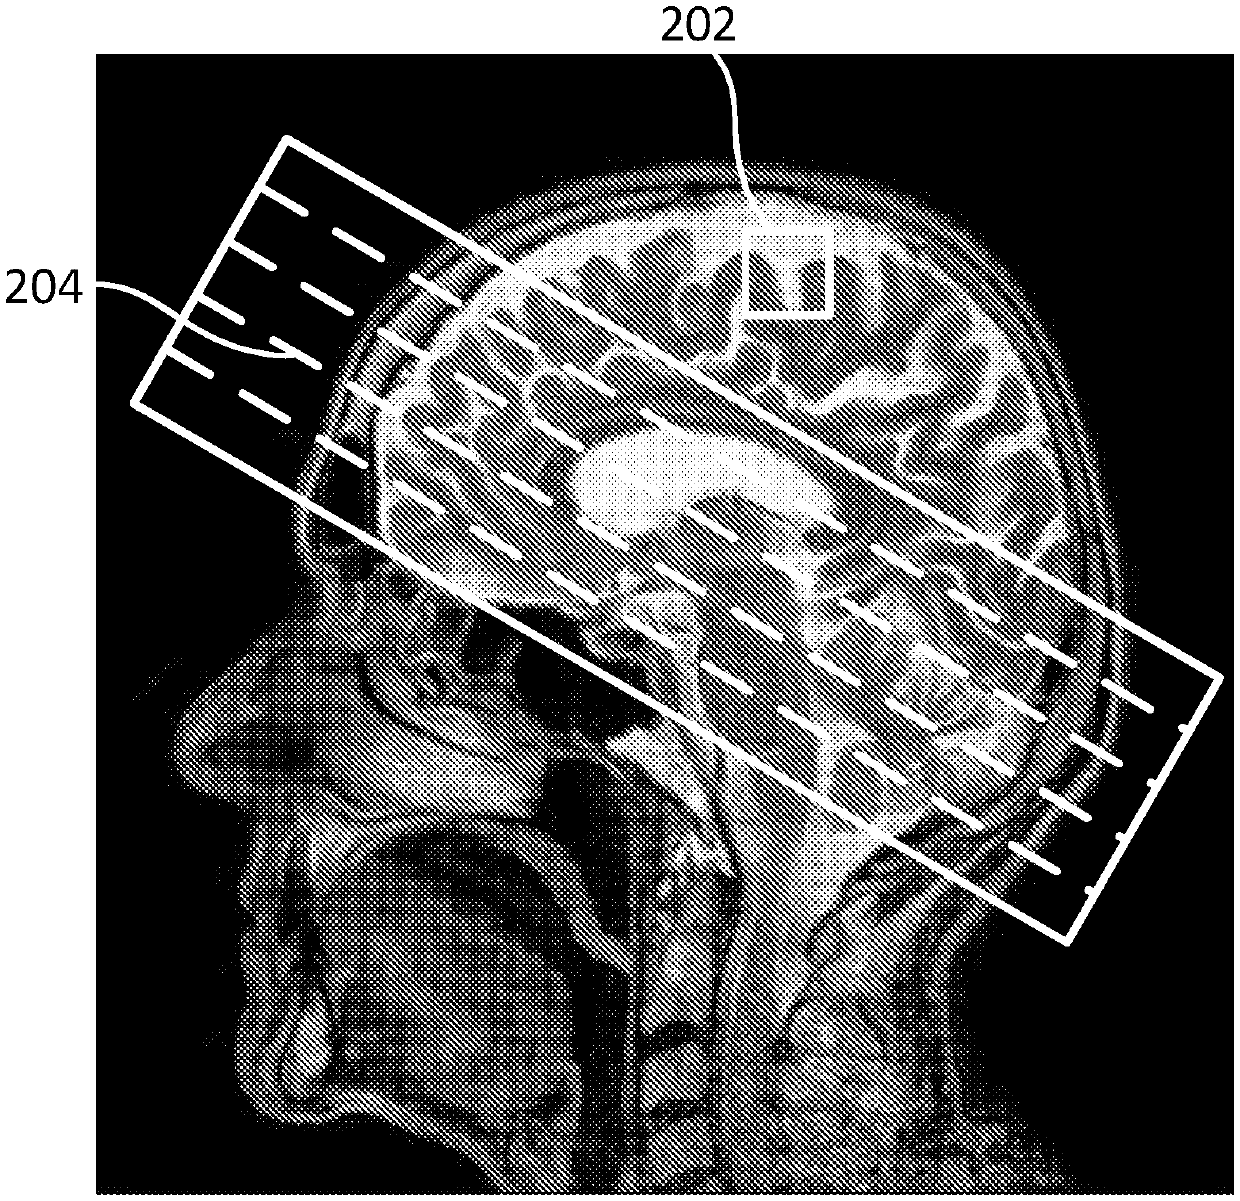

Temperature measurement in thermal therapy